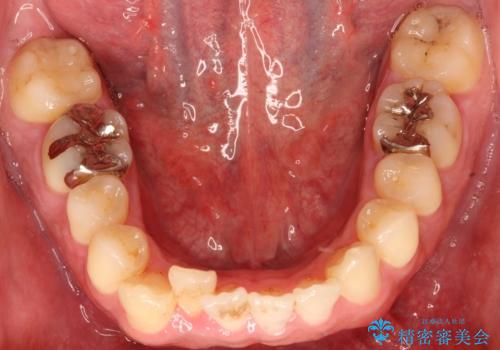

- 出っ歯が気になるとのことで来院されました。

上顎の前から4番目の歯を両側、合計2本抜歯して矯正する計画としました。

目立たない装置がご希望でしたので、上下裏側ワイヤー装置を選択されました。